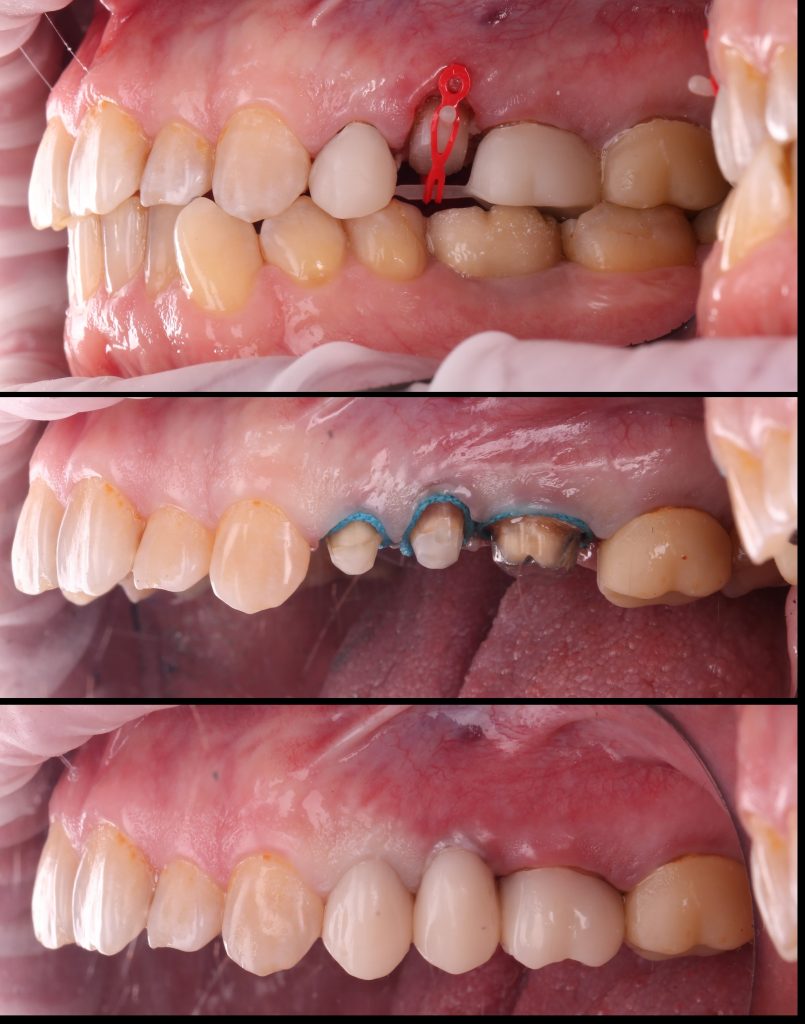

Поведено эндодонтическое лечение

Был получен достаточный объём твердых тканей над уровнем десны, что обеспечило создание феррул-эффекта. Первый этап ортопедической реабилитации завершен фиксацией временных конструкций